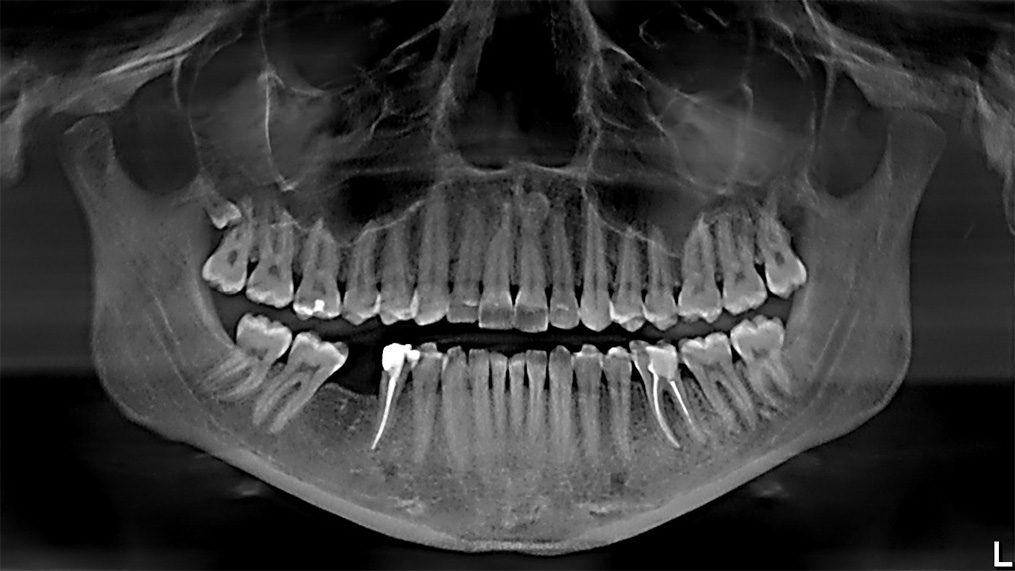

-What is the name of this image?

-Make a diagnosis?

-Write 3 ways to treat it?